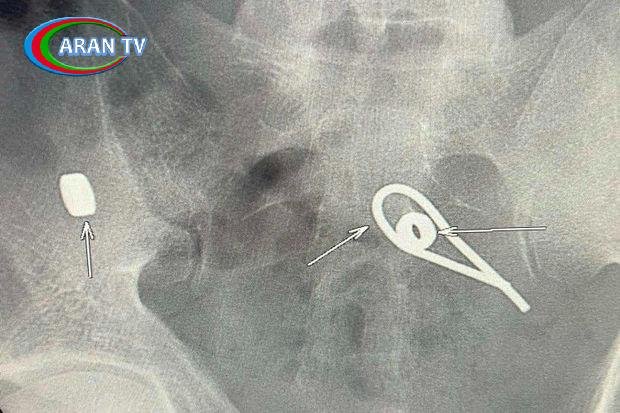

Lent.az xəbər verir ki, bir kişi intihar etmək məqsədilə iki metal qayka və bir ədəd əyilmiş məftil udub.

O dərhal xəstəxanaya yerləşdirilib. Rentgen müayinəsi zamanı kişinin bağırsaqlarında udduğu metal parçalarının yeri müəyyənləşib. Hazırda həkimlər metal əşyaların çıxarılması üçün tədbirlər görürlər.